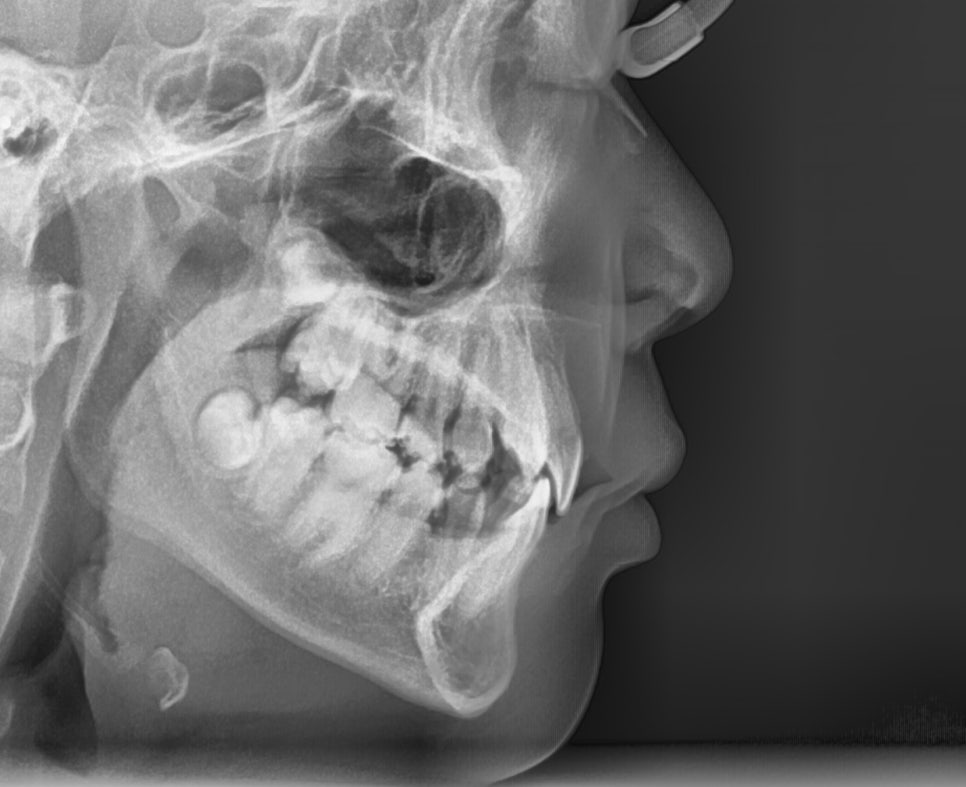

측면 세팔로 엑스레이에서는

앞니 각도가 안쪽으로 기울어져 있는

옥니 상태였습니다.

더불어, 오른쪽 위 측절치는 반대교합,

송곳니는 덧니처럼 맹출 되어

기능과 심미 모두에 문제가 있었죠.